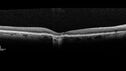

77 year old female HPI: CC: Decreased Vision OU. Since Last Visit: worsening. Location: central vision. Context nset/Aggravation: while reading. Modifying Factors: when closes one of her eyes notices letters are missing. Duration of Problem: couple of months. Associated Symptoms: foggy circle temporal when driving OU. Severity: moderate. Course: intermittent . HPI obtained by Steven M. Cohen, MD, FACS Medical Hx: Hypertension, Systemic. Hyperlipidemia. Depression. Spinal Stenosis. Psoriasis. Osteopenia Systemic Meds: TIZANIDINE HCL. TRAMADOL HCL prn. ZOLPIDEM. HYDROCORTISONE. TRAZODONE HCL, Clobex 0.05 % Topical Spray. VA OD 20/32, OS 20/20 IOP 13 OU